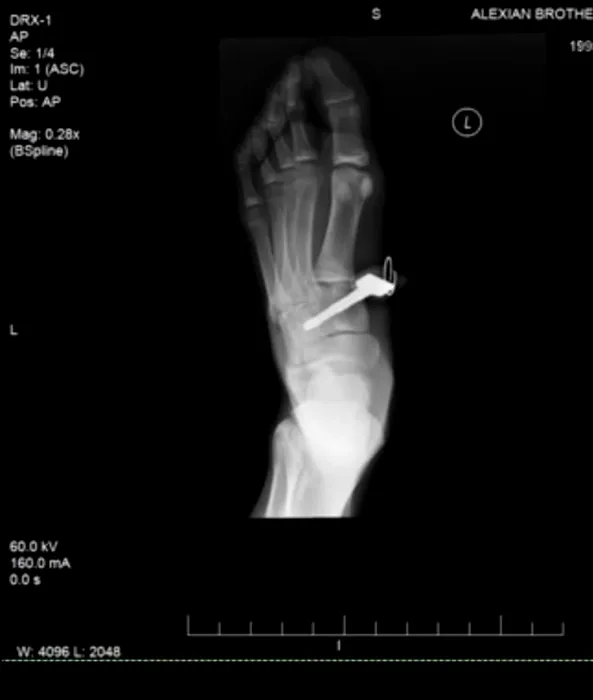

Accidentul teribil al unui tânăr karatist în timpul antrenamentelor. VIDEO